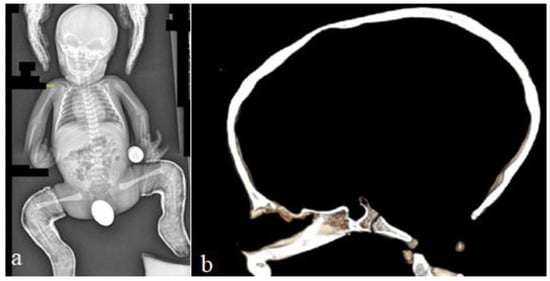

The 14-months-old boy was referred to our consultation for a clinical assessment and diagnosis. The clinical examination revealed a growth deficiency of -2SD, pseudo-hydrocephalus with a prominent forehead, deep seated eyes and sparse hair. Down slanting palpebral fissures, a beaked nose with a protruding nasal septum below the hypoplastic nares, low set ears and thin lips were notable features. The thin upper lip was associated with retrognathia. The limbs were short, the thumbs were relatively short and wide, the hallux was wide and the rest of the digits of the hands and feet were short. Relative hemi-hypertrophy could be elicited. The hands were with relative camptodactyly. A musculoskeletal examination showed moderate ligamentous hyperlaxity. The intellectual performance was difficult to assess, though his smile was somehow associated with peculiar facial expressions overwhelmed by a bizarre facial grimacing when trying to smile. The skeletal survey and lateral skull radiograph showed a very large anterior fontanelle (massive defective ossification) associated with frontal bossing, giving the impression of pseudo-hydrocephalus. There were also hyperostosis of the skull base and Wormian bones along the lambdoid sutures (Figure 4a). An AP skull radiograph showed the frontal bossing and the persistence of the anterior fontanelle (Figure 4b). Genetic testing was not performed for this patient. A 2-year-old boy presented with the phenotype and genotype of RSS. He underwent a 3D reconstruction CT scan to assess the anatomy of the skull and the anterior fontanelle. A 3D reconstruction CT scan of the skull (anterior view) of the 2-year-old boy showed frontal bossing and the persistent open anterior fontanelle (Figure 5a). A 3D reconstruction of the crown of the skull of the same boy showed a defective ossification of the anterior fontanelle and a defective and disorganized ossification of the skull bones (arrows) (Figure 5b). Hypomethylation of the imprinting control region (ICR1) on chromosome 11p15 and maternal uniparental disomy of chromosome 7 was encountered.

Figure 5. Three-dimensional reconstruction CT scan of the skull (anterior view) of a 2-year-old boy with RSS showed the frontal bossing and the persistent open anterior fontanelle-(arrow) (a); Three-dimensional reconstruction of the crown of the skull of the same boy showed defective ossification of the anterior fontanelle and defective and disorganized ossification of the skull bones (arrow heads) (b).